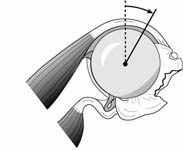

In this release the anterior capsule is incised just lateral to the labrum leaving the labrum on the bony glenoid to maintain the glenoid concavity. After the release the subscapularis should have a nice ‘bounce’ when traction is applied to it. Recall that if the subscapularis is to allow a range of rotation of 115 degrees (two radians), it must have an excursion of twice the radius of the humeral head. Thus, if a humeral head has a radius of 25 mm, a subscapularis excursion of 50 mm will allow a 115-degree range of internal and external rotation. [See Figure 7]